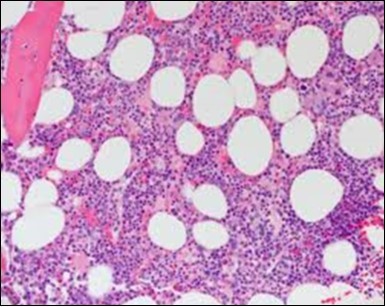

Figure 3.HCL: hairy cells dispersed within the native architecture(19).

The classic hairy cell is medium sized with a magnitude of 10-14µm. The moderately abundant or variable cytoplasm may be transparent or mildly basophilic. The cellular surface with the characteristic serrated perimeter depicts innumerable fragile or stout extensions of cytoplasm ,particularly discernible on the phase contrast and electron microscopy. The cytoplasm may exhibit vacuoles with occasional azurophilic granules4. The nucleus may be elliptical or reniform, folded or indented with a coarse, reticulated or a finely dispersed chromatin and inconspicuous nucleoli along with infrequent mitosis. Bone marrow aspiration or bone marrow trephine biopsy may be inadequate for diagnosis in 30%-50% individuals4. The trephine sections of the bone marrow may depict a characteristic interstitial pattern of leukaemic infiltration. Generally the bone marrow is hyper-cellular, though it may be hypo-cellular in 10-15% individuals4. The leukaemia cell ingress may be diffuse or partial, although diffuse infiltration is frequent. The partial variety of leukaemic dissemination may be ineptly categorized with an indeterminate differentiation from the uninvolved marrow. The malignant insertions may initially emerge as miniature, undefined, cellular loci. The formalin fixed, paraffin embedded sections may elucidate a crystalline zone or a “halo” appearance of the cells with a circumscribed nucleus on account of the plentiful cytoplasm4. The cellular margins may be intertwined. Fixation of bone marrow smears with Zenker’s fixative may demonstrate a retracted cytoplasm of the hairy cells with a consequent disconnected structure. The bone marrow in the absence of a malignant process may be hypo-cellular or hyper-cellular. Reticulin stains may delineate an enhanced accrual of broad, dense reticulum fibres surrounding the aggregates of leukaemia cells with the fibrous circumlocution of individual malignant cell and fibrotic extensions into the abutting, uninvolved bone marrow4.

The leukaemia cells may enunciate a characteristic immune phenotype, crucial for a confirmatory diagnosis. The peripheral blood mononuclear B cell population may display a kappa or lambda light chain restriction. The phenotype of classic hairy cell leukaemia may be delineated by concurrent, immune reactive CD19+ CD20+,CD 11c+, CD25+, CD103+ and CD123+. An intensely immune reactive CD200+ and a non reactive CD27- antigen may be present2, 4. Evaluation of a trephine bone marrow biopsy and bone marrow aspirate may define the degree of tumour infiltration. A dry tap on account of prominent bone marrow fibrosis may be elucidated at preliminary diagnosis. A decline in the normal haematopoiesis may account for a hypo-cellular marrow in 10% instances. Gradation of cellular infiltrating of the leukaemia within the bone marrow may be appropriately investigated with immune –histochemical stains2, 4. Immune staining for CD20+, annexin 1 and VE1 (a BRAF V600E stain] may validate the diagnosis and precisely analyse the extent of malignant bone marrow infiltration[8]. Determination of BRAF V600E mutation may be critical in therapeutically non responsive individuals with applicable standard therapy or in instances of multitudinous reoccurrences[9]. Deploying inhibitors of BRAF V600E gene may be efficacious in patients impervious to approved therapy. The mutation necessitates a comprehensive scrutiny of the implicated individuals with a sensitive molecular assay which may discern up to < 10% of the hairy leukaemia cells appearing in the peripheral blood smears or bone marrow aspirates diluted with peripheral blood or aspirates elucidating a dry tap[2,4]. Allele specific polymerase chain reaction (PCR) or a next generation sequencing may be optimally employed to circumvent false negative outcomes. If the leukaemia cells are sparse or if particularly sensitive & efficacious molecular techniques are not accessible, the application of appropriate immune histochemical stains to the bone marrow biopsy such as a BRAF V600E mutation stain (VE1) may detect the hairy cells and conclusively diagnose the condition[2,4,10]. Figure 1, Figure 2, Figure 3, Figure 4, Figure 5, Figure 6, Figure 7, Figure 8, Figure 9, Figure 10, Figure 11, Figure 12, Figure 13, Figure 14.